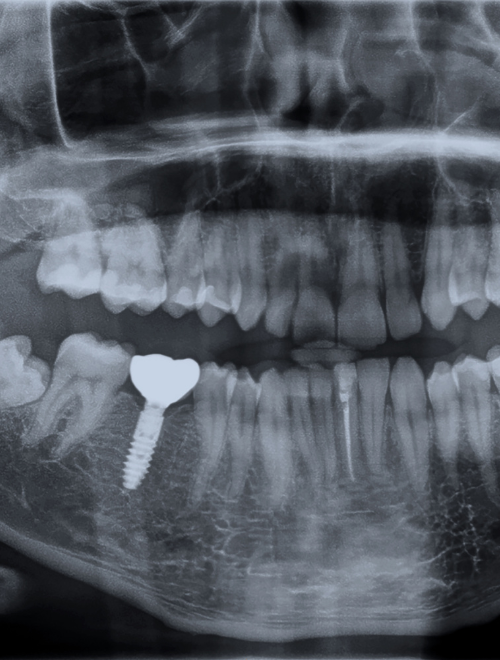

Pojedynczy implant

Idealne rozwiązanie w przypadku braku jednego zęba. Polega na wszczepieniu śruby (implantu) i zamocowaniu na niej korony ceramicznej.